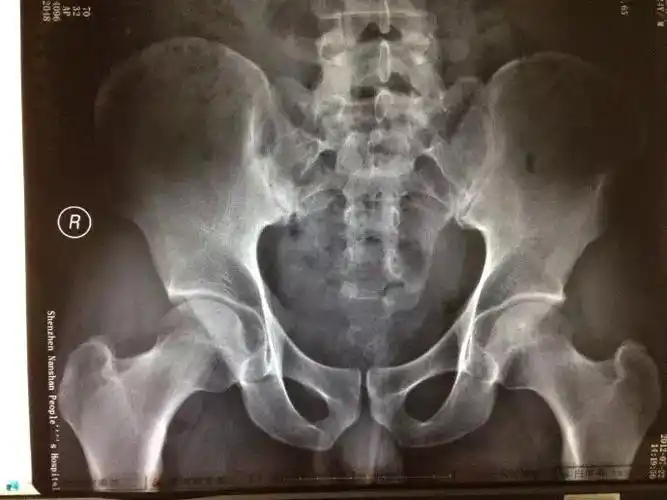

骶髂关节错位ppt

腰痛站桩站出来的骶髂关节错位

请问是不是骶髂关节错位骨盆有没有旋转